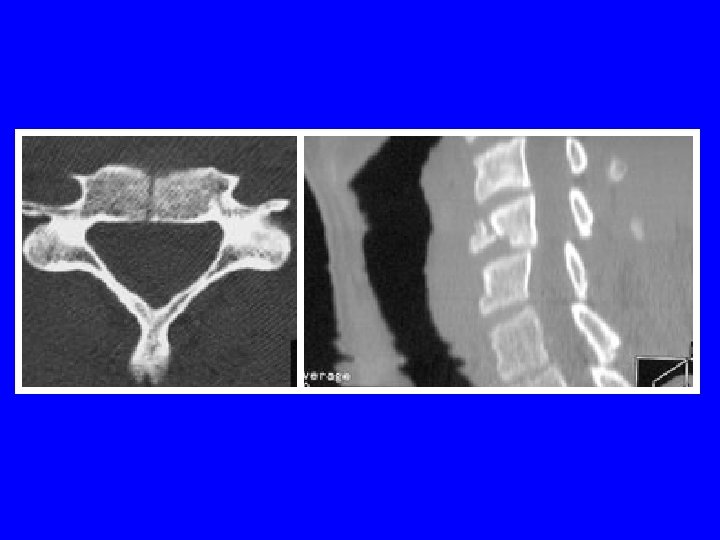

LESIONS DISCO-CORPOREALES Burst fracture: considérées comme stables et peu neuroagressives Si perte hauteur du corps> 40% et cyphose local > 15°: chirurgie